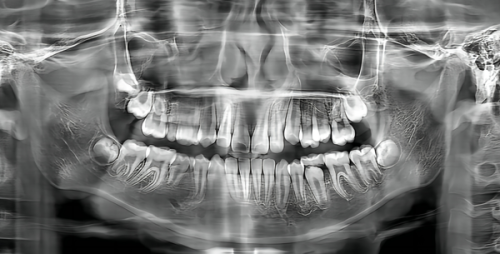

蛀牙属于牙体硬组织的慢性疾病,主要是细菌侵蚀牙釉质、牙本质导致的缺损,治疗核心是修复缺损、终止病变,这类诊疗属于口腔内科范畴。在综合医院里,大多没有过于细分的口腔科室,直接挂口腔科就能完成补牙诊疗,医生会先检查蛀牙的重度程度,判断是直接补牙还是需要根管治疗等后续处理。

在大型口腔专科医院,科室划分更精细化,会把口腔疾病分为牙体牙髓科、牙周科、口腔外科等,此时蛀牙补牙就可以挂牙体牙髓科,这个科室专门处理牙体硬组织和牙髓的疾病,医生在蛀牙诊断、补牙材料选择、复杂蛀牙处理(比如深龋接近牙髓、牙髓炎前期)上更有针对性,诊疗流程也会更专精。需要明确的是,蛀牙补牙不需要挂口腔外科,因为口腔外科主要负责拔牙、口腔颌面手术、智齿拔除等有创手术类项目,补牙属于修复和保守治疗,和外科范畴无关。